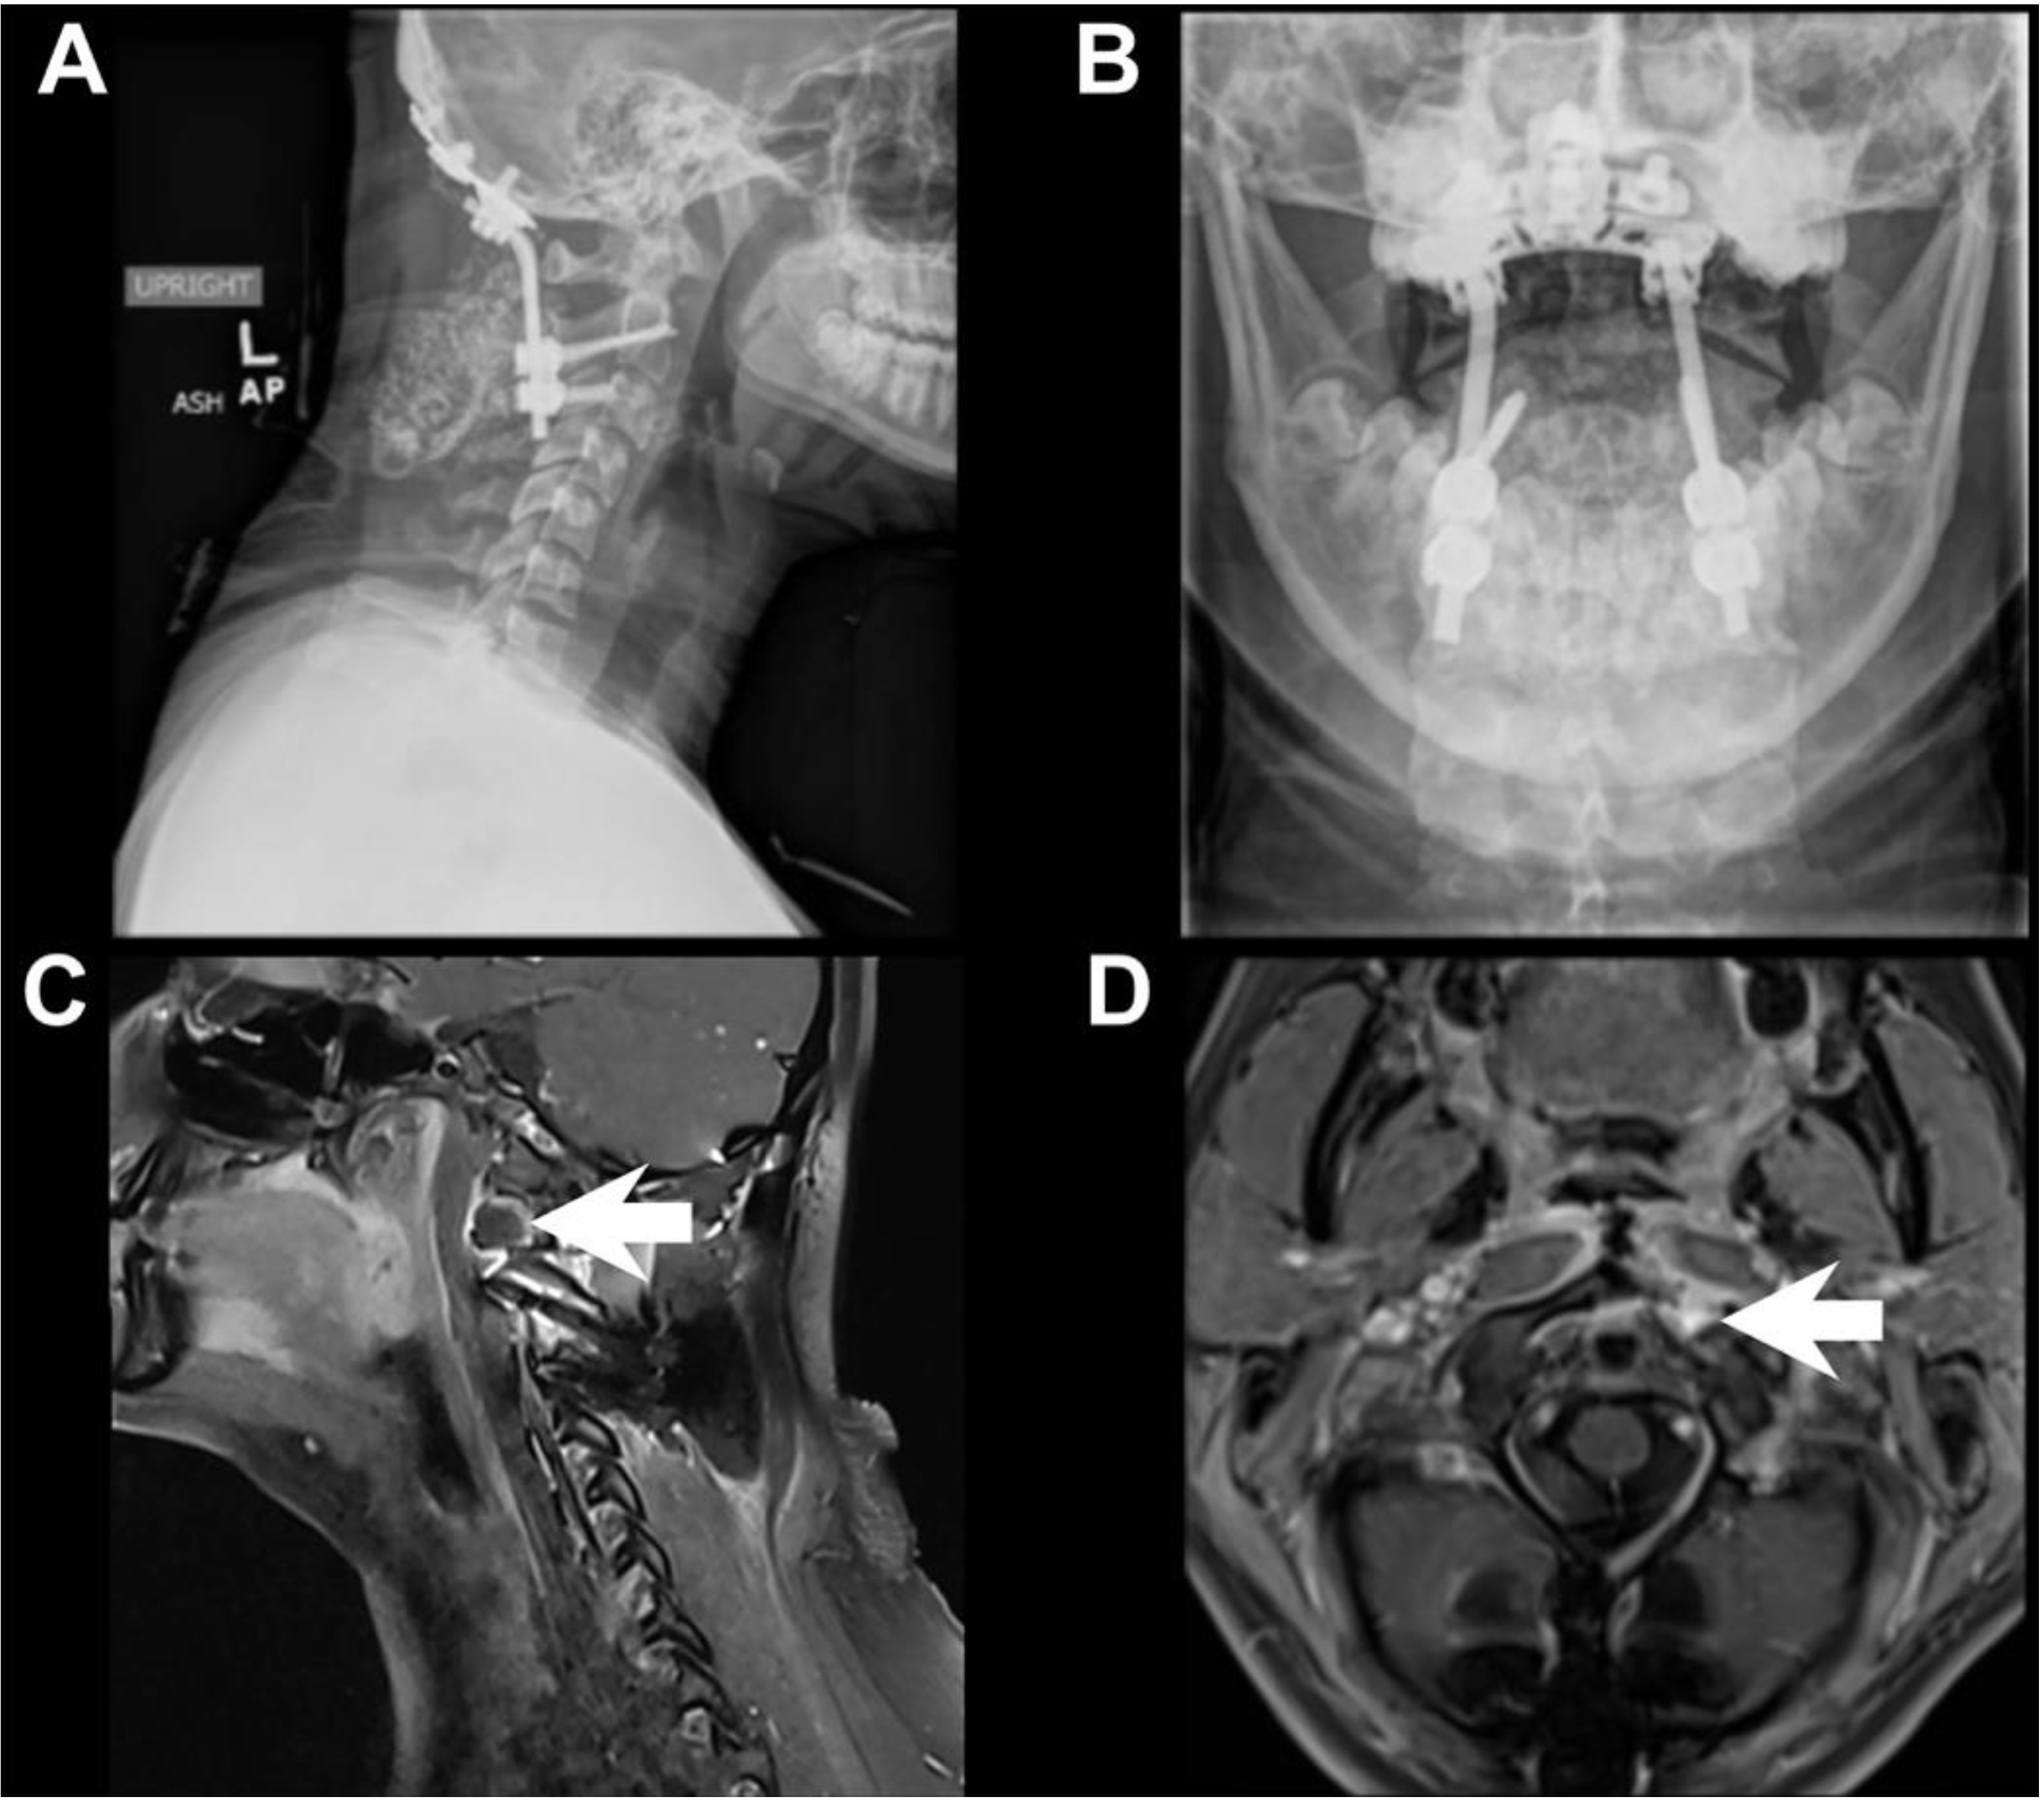

2. Case Description